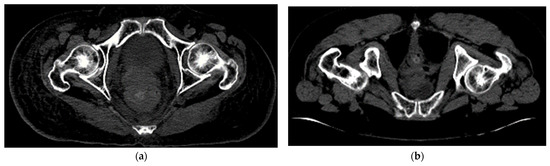

3.2. Contrast Enhancement and Femur Cropping

3.3. Cropped CT Slices Augmented with Attributes (Feature Addition)